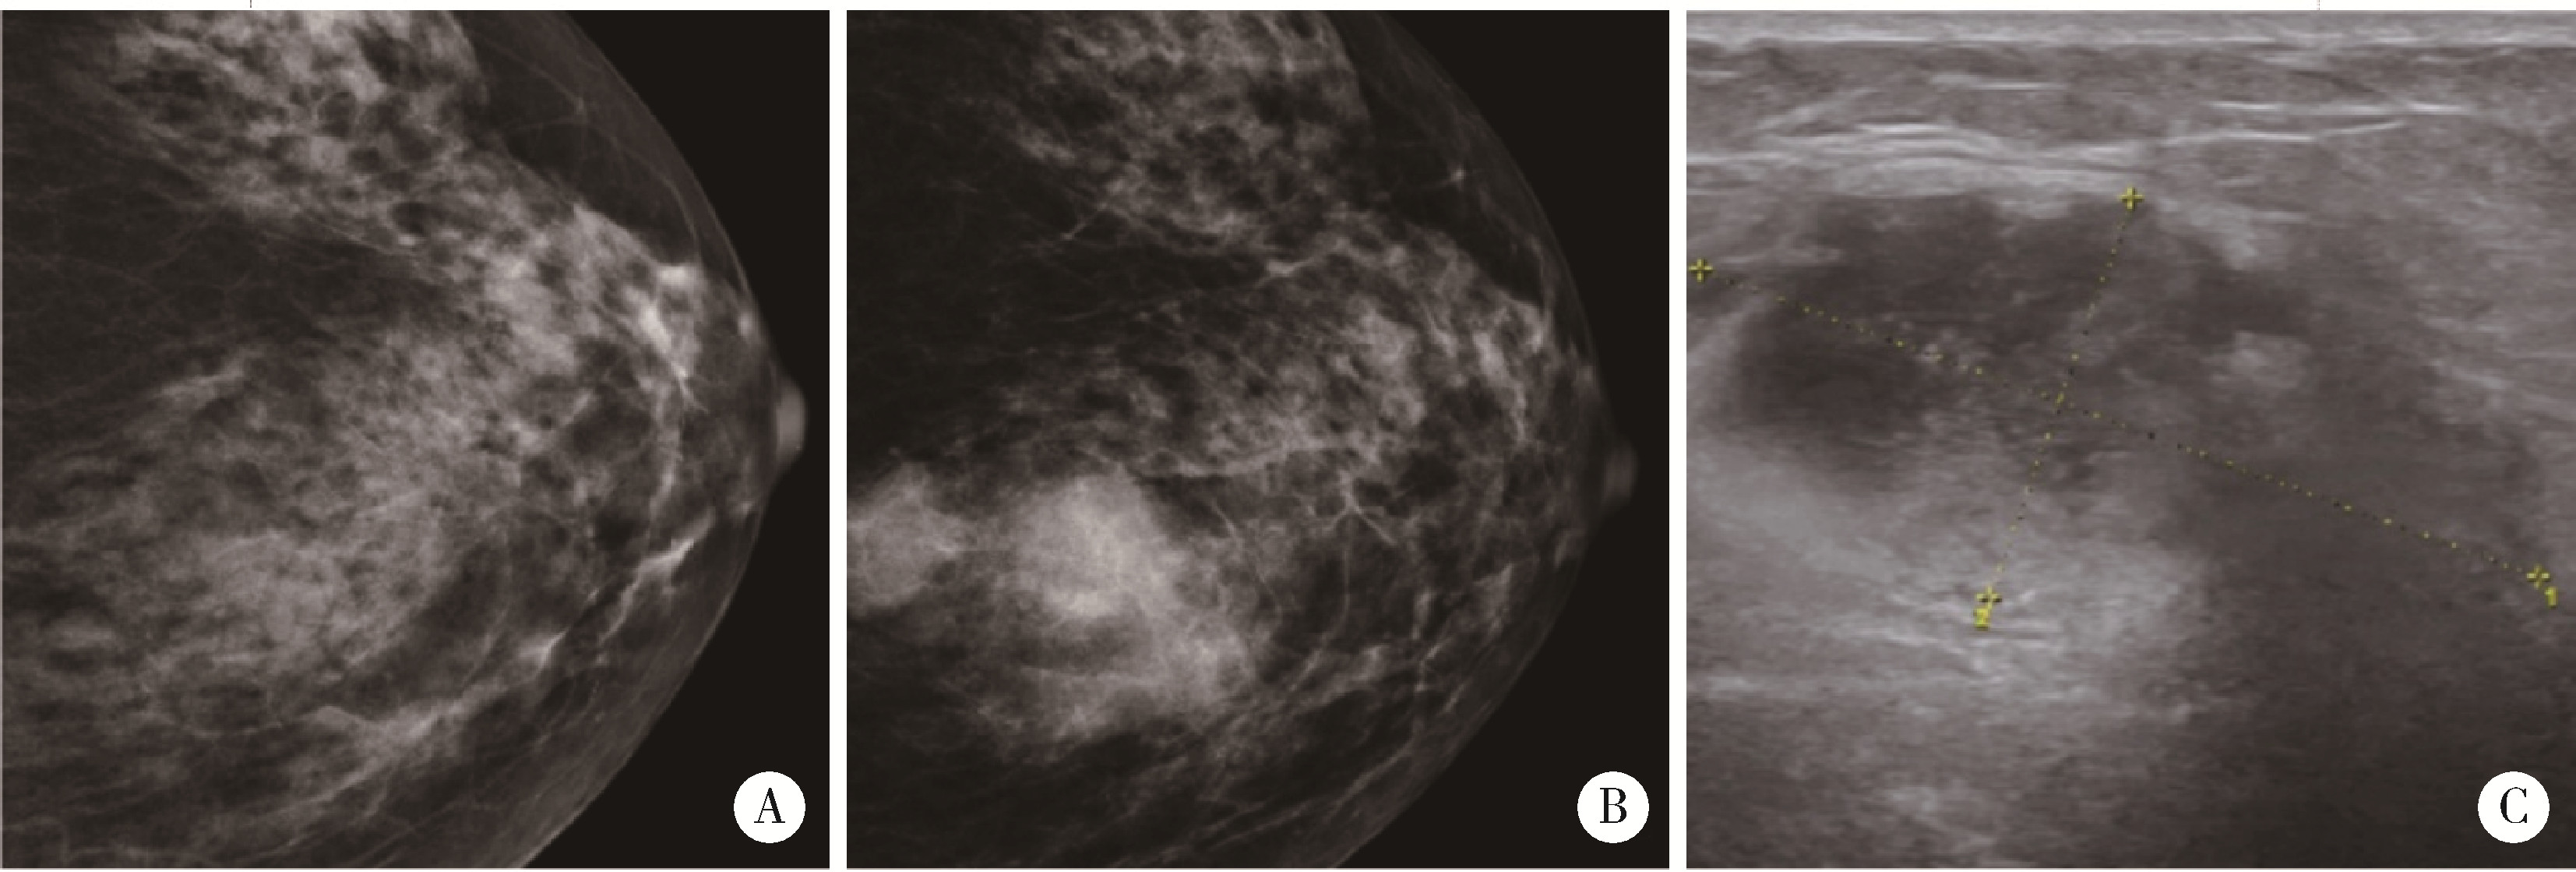

Figure 2

Left breast mass examination A, mammogram (October 2021), multiple flaky or slightly high-density shadows are observed, with no apparent tumor identified; B, mammogram (October 2023), multiple circular and slightly high-density shadows are noted in the upper quadrant, approximately 8.5 cm from the nipple. The most extensive lesion measures approximately 3.5 cm×2.6 cm, with slightly blurred margins (Assessment: BI-RADS 4C); C, breast ultrasound (October 2023), a hypoechoic mass measuring 4.0 cm×1.9 cm is identified, exhibiting an irregular shape, indistinct margins, and no significant posterior acoustic changes (Assessment: BI-RADS 4B)."